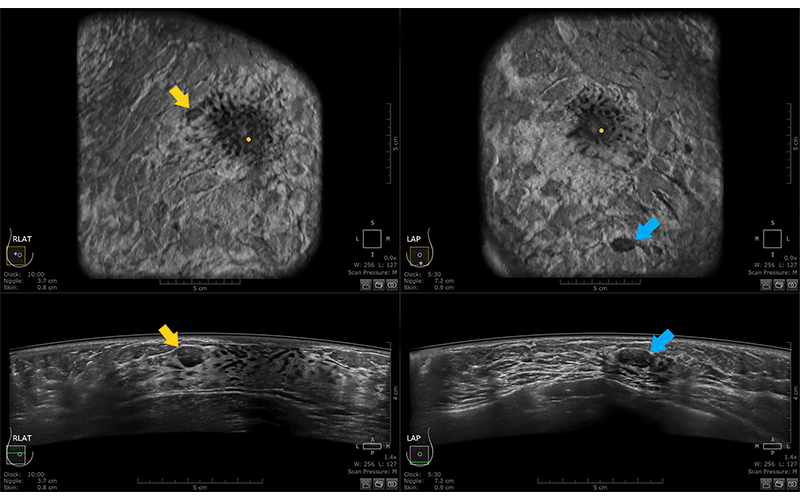

Multiple bilateral benign masses in a 44-year-old woman who presented for baseline screening AUS. Both coronal (top) and transverse (bottom) images from the LAT data set of the right breast (left) and the AP data set of the left breast (right) are shown. Oval, circumscribed, hypoechoic masses with parallel orientation are visualized in the upper outer right breast (yellow arrow) and the lower left breast (blue arrow). The patient had additional similar-appearing masses bilaterally, which fulfills criteria for a benign finding, or BI-RADS category 2. https://doi.org/10.1148/rg.230023 © RSNA 2023